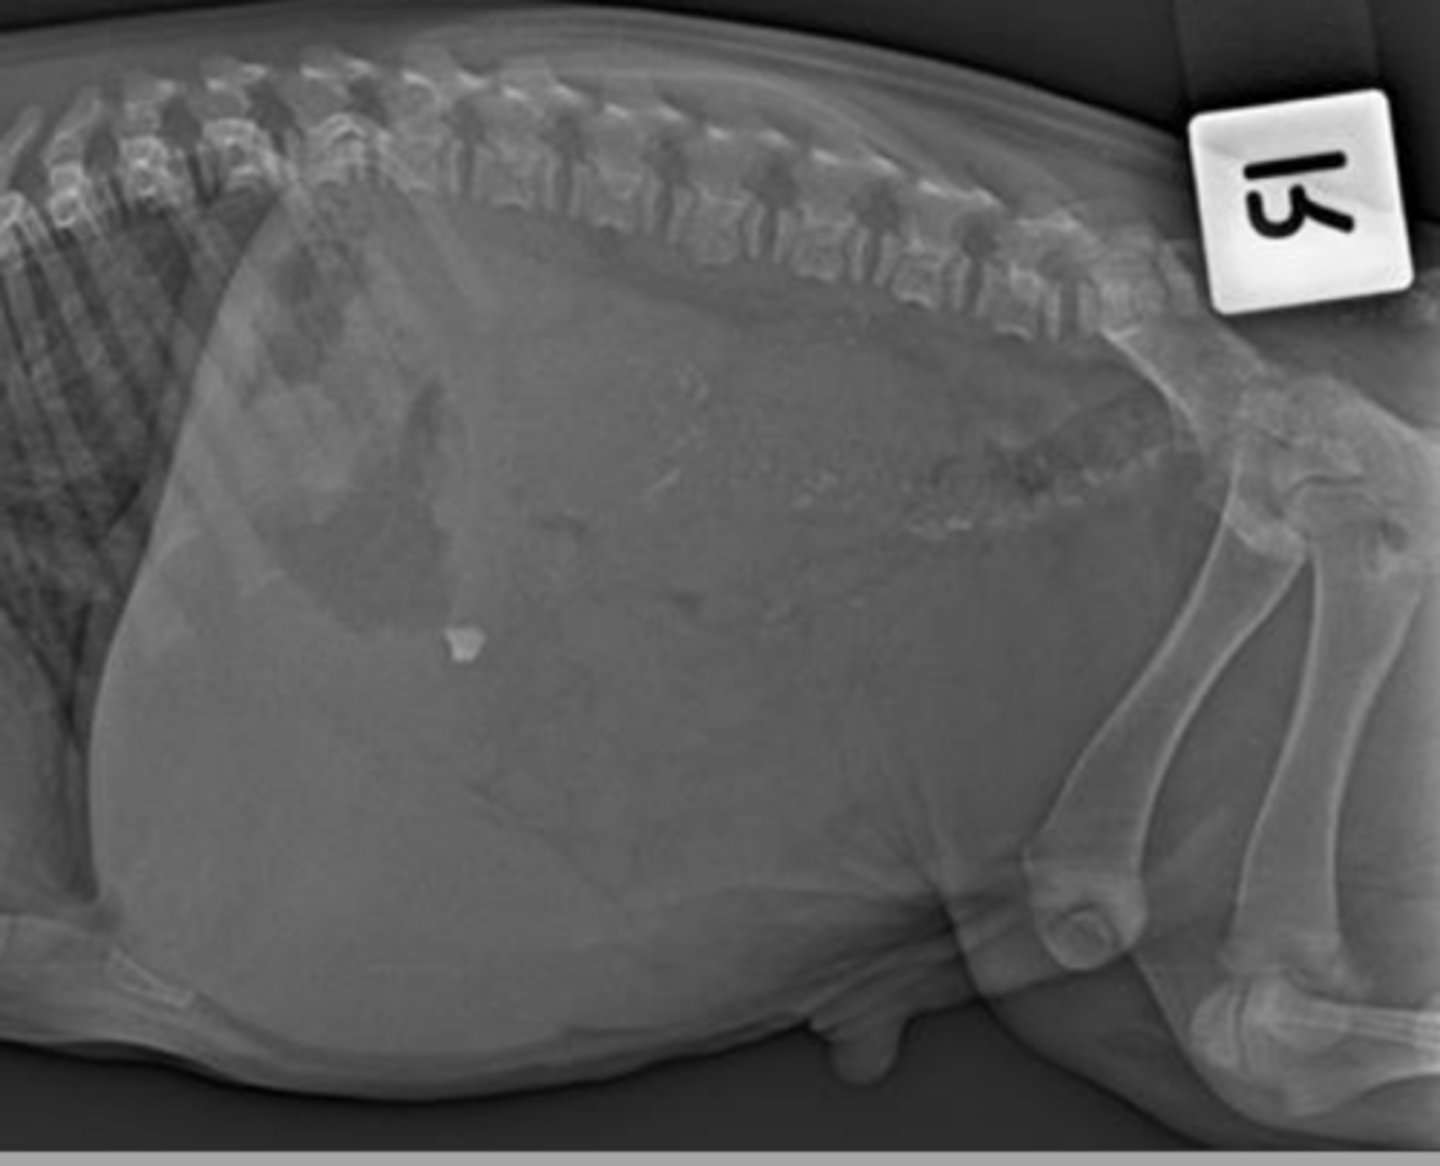

What body cavity do you take an x-ray of when the patient is at peak expiration?

abdomen.